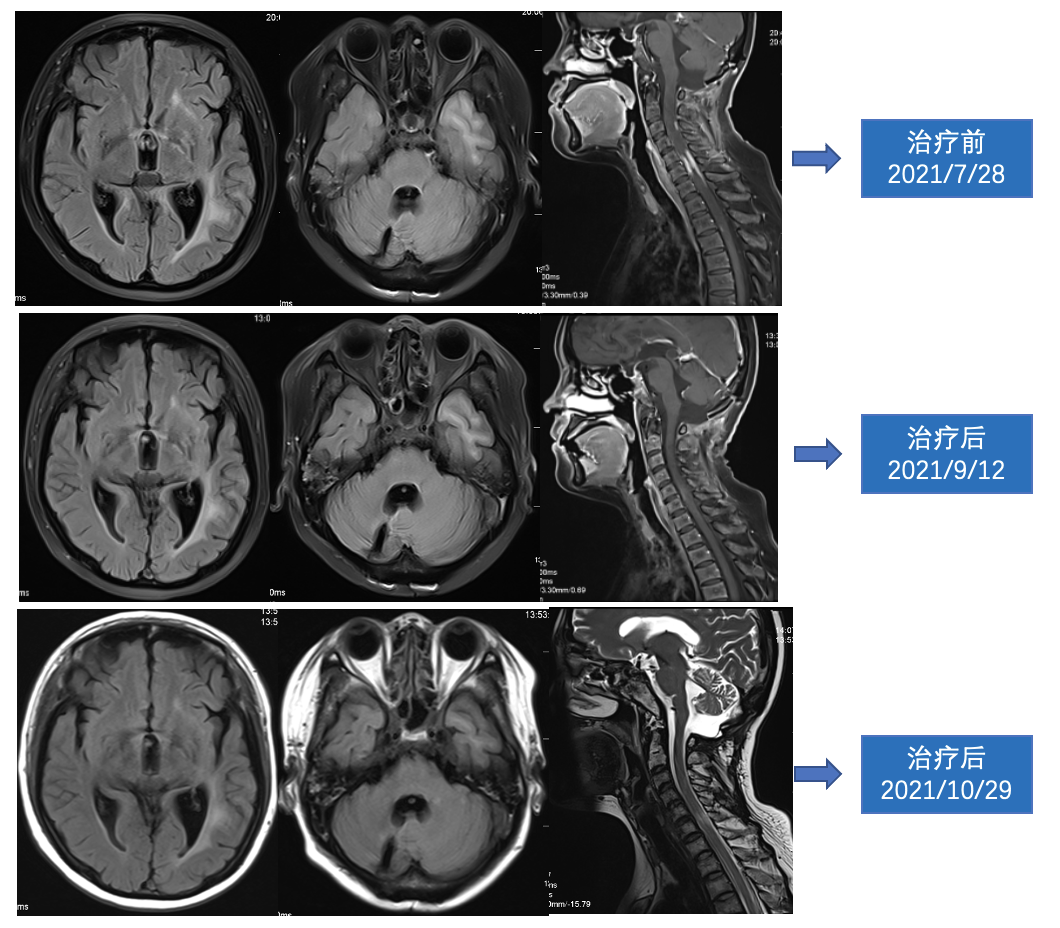

影像学资料

MRI(2021.9.12)示:双侧顶枕颞叶、胼胝体、双侧基底节区多发异常信号,强化较前范围缩小;颈髓及胸髓上段局部略增粗,相应髓腔内结节状及斑片状强化影,强化范围较前缩小。

MRI(2021.10.29)示:双侧顶枕颞叶、胼胝体、双侧基底节区多发异常信号,较前部分缩小;颈髓及胸髓上段局部略增粗,相应髓腔内结节状及斑片状强化影,强化范围较前缩小,部分显示不清。